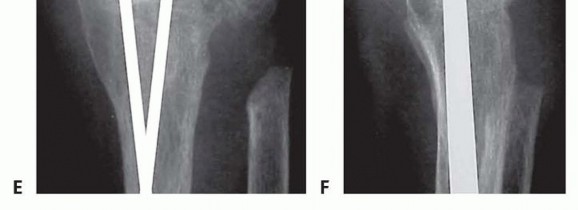

Intramedullary Rod Osteosynthesis

In scenarios where plate fixation is contraindicated—such as in severe rheumatoid arthritis with profound osteopenia, compromised dorsal soft tissues, or when a neutral wrist position is specifically desired—intramedullary rod osteosynthesis is an excellent alternative. Following identical joint preparation, a stout Steinmann pin (typically 1/8 inch or 3.2mm) is utilized. The pin is introduced retrogradely. It is driven distally through the capitate and down the medullary canal of the third metacarpal until it exits the metacarpophalangeal (MCP) joint with the joint held in maximal flexion. The pin is then advanced until its proximal tip is flush with the proximal articular surface of the capitate.

Image

The wrist is then carefully reduced into a neutral alignment. The Steinmann pin is driven proximally, crossing the radiocarpal joint and advancing deep into the medullary canal of the distal radius. Fluoroscopy is critical to ensure the pin remains centrally located within the radial canal and does not breach the volar or dorsal cortices. Often, a second, parallel or slightly divergent pin is placed through the second or fourth metacarpal to provide rotational stability to the construct. The distal ends of the pins are cut flush with the metacarpal head beneath the articular cartilage, or left slightly prominent dorsally for planned removal once radiographic union is achieved. The dorsal capsule is then meticulously repaired over the hardware, and the EPL tendon is left transposed in the subcutaneous tissues prior to layered skin closure.